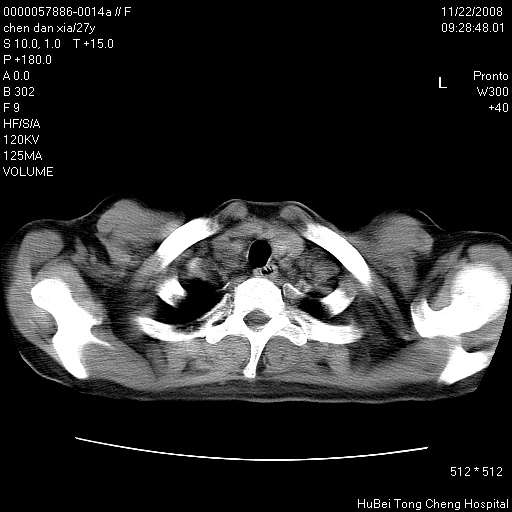

标题: CT16752:F,27Y。发热咳嗽20余天,伴盗汗。 [打印本页]

标题: CT16752:F,27Y。发热咳嗽20余天,伴盗汗。

建议强化观察,考虑肺门及纵隔淋巴结结核。另外还需结合实验室检查。

气管前腔静脉后淋巴结肿大 右肺门纹理模糊

淋巴结核?

右下肺纹理模糊;纵隔可见肿大淋巴节;右心缘旁结节,边缘光滑,纵隔窗病变范围较肺窗明显小,首先考虑右下肺结核,不排外淋巴瘤

下肺结节,结节内钙化,肺门纵隔淋巴肿大 结核可能性大

气管旁,两肺门可疑淋巴结肿大,建议ct增强.